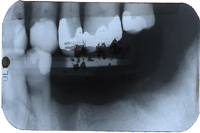

Hier handelt es sich um einen 61 Jahre alten Patienten. Im Röntgenbild von Abb. 1 sieht man den zahnlosen Unterkiefer. Die Oberkieferbackenzähne haben keine Funktion. Der Patient wünscht keinen abnehmbaren Zahnersatz. Auf dem Modell (Abb. 2) ist allerdings ersichtlich, dass der Kiefer viel zu schmal ist für ein Zahnimplantat: nicht einmal 5 mm, was eine Knochenbreite von 3 mm nach der Aufklappung ergab (2 mm Schleimhaut).